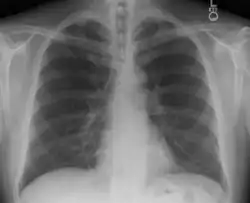

Рентгенограмма грудной клетки в прямой проекции, норма.

Рентгеногра́фия органов грудной клетки — классическое проекционное рентгенографическое исследование грудной клетки, применяемое для диагностики патологических изменений грудной клетки, органов грудной полости и близлежащих анатомических структур. Рентгенография грудной клетки является одним из наиболее распространённых рентгенографических исследований.

При изучении рентгеноанатомии органов грудной клетки обращают внимание на рентгеновскую структуру видимых костей и мягких тканей грудной клетки; форму и прозрачность для рентгеновских лучей областей, на которые проецируется лёгочная ткань (так называемых «лёгочных полей»), а также их структуру, сформированную тенями сосудов лёгких («лёгочный рисунок»); расположение и структурность корней лёгких; положение, форму куполов диафрагмы и синусов плевральных полостей; форму и размеры тени средостения (в том числе сердца).